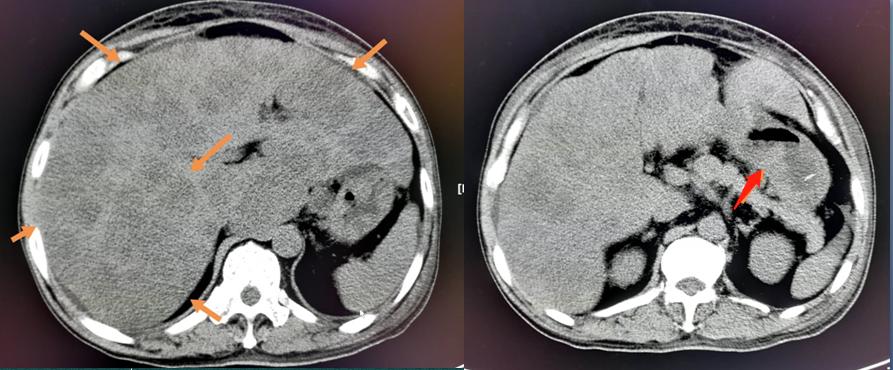

上图是今天的另外一位病人,才60岁,腹痛半个月,做了CT和胃镜,胃癌,已经广泛转移了,肝脏几乎被转移的癌细胞占满了。

他有多年胃病,如果2年前做一次胃镜检查,有很大可能躲过这一劫……